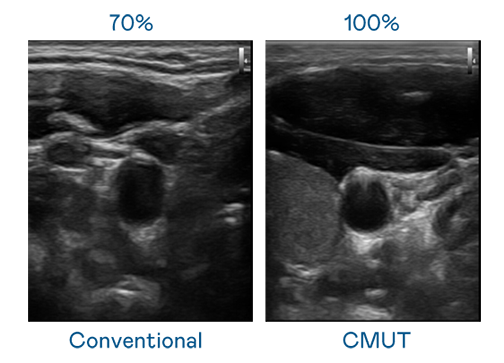

CMUT 技术是一种用电容式微机电元件来产生超音波讯号的技术。与传统 PZT 压电式技术相比,CMUT 频宽增加 30%,更宽频的超音波讯号让影像解析度大幅提升,是实现高影像品质医疗超音波扫描、促进精准医疗发展的关键技术。

大频宽带来超清晰影像

超音波影像的解析度高低,首先取决于探头能发出的讯号频宽。vinbet浩博 CMUT 可提供高清晰的超音波讯号,提供高频宽、高灵敏度、影像纹理细节更高的超音波影像,协助医护人员缩短影像判读时间及利用精准的医疗影像进行诊断。